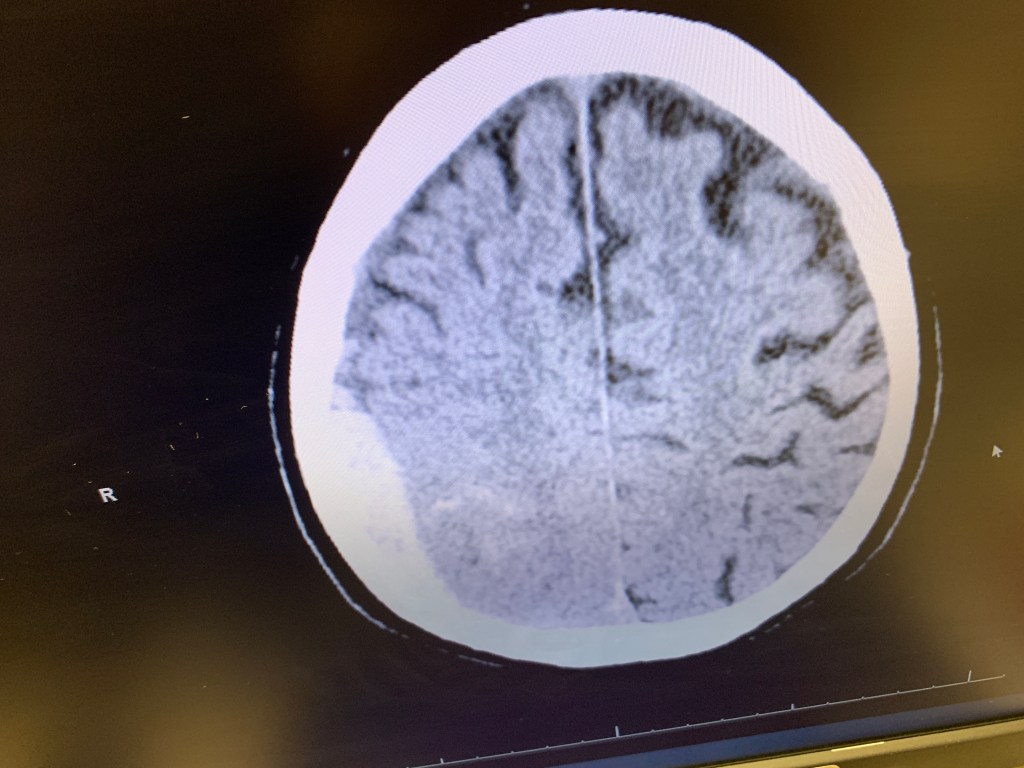

Here we look inside my husband’s brain

a mandala a network of pathways interfacing in his head.

his brain is bleeding

a hematoma lies on top of the right hemisphere

yes, the brain is divided into right and left hemispheres